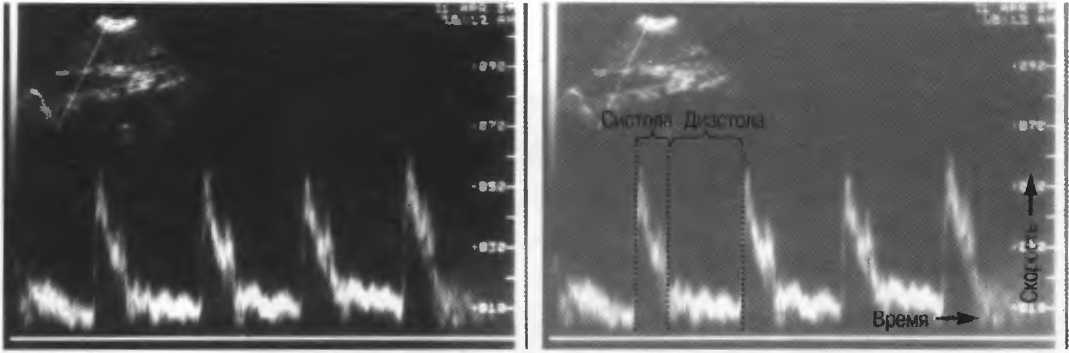

2. В импульсном режиме доплерографии ультразвук излучается импульсами с хорошим разрешением по глубине. При этом имеется возможность избирательного измерения скорости кровотока в отдельном сосуде (рис. 2а). Недостатком данного режима является невозможность измерения высоких скоростей потока в глубокорасположенных сосудах, а также возможность искажения спектра скоростей кровотока, когда высокоскоростные потоки ошибочно изображаются как низкоскоростные.

Рис.2а. Доплерографическое исследование в импульсном режиме, регистрирующее скорость кровотока чуть выше уровня бифуркации аорты.